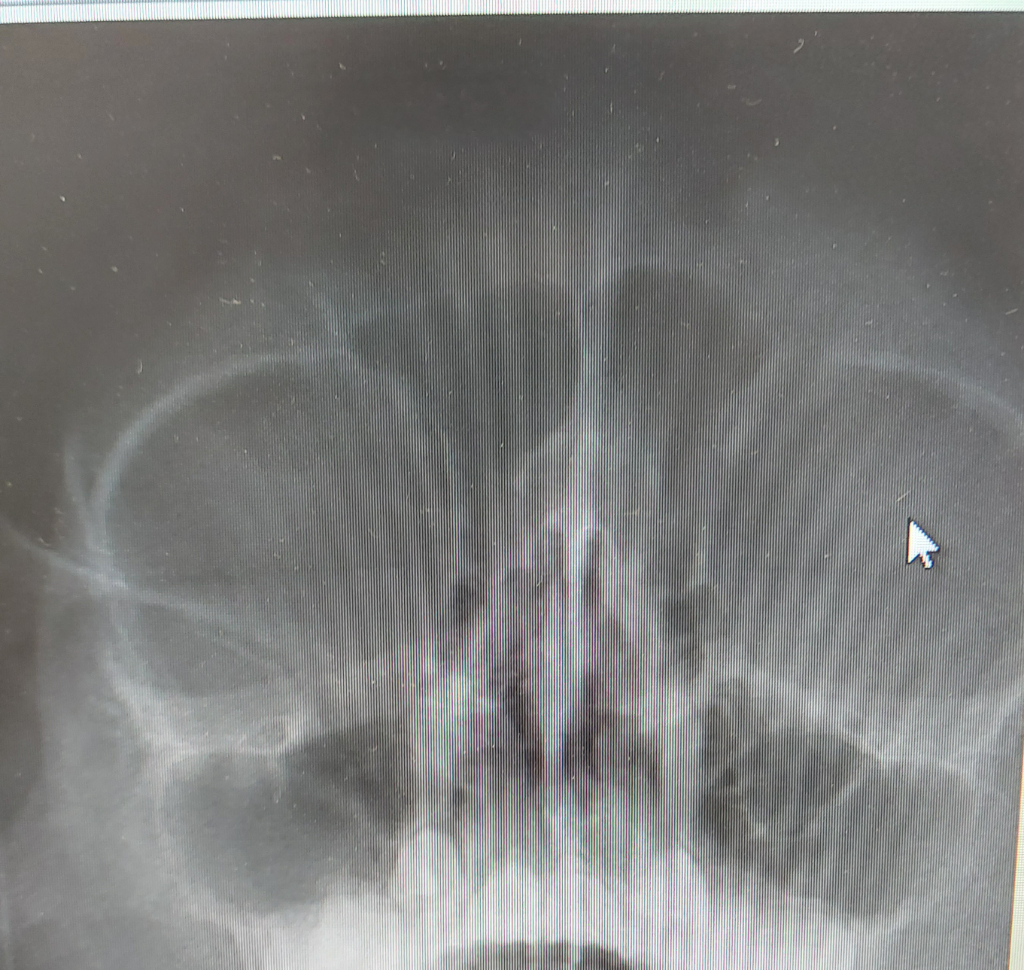

부비동 엑스레이 사진 부탁드립니다

9살아이 부비동 사진입니다. 농이 빠졌다고 볼수 있나요

반복되는 축농증이 있는 친구입니다. 전체적으로 검은색은 아닌데 뒤에 구조물땜에 저렇게 보일수 있는걸까요

이전과 비교하여 보는 것이 가장 확실하겠으나 부비동안에 고여있는 농은 보이지 않아 빠진 것으로 생각됩니다.

화질이 좋지 않고 엑스레이 전용프로그램으로 보는 것이 아니여서 정확하다고 말씀드리긴 어렵지만 사진 상으로는 부비동염이 호전된 것으로 생각됩니다

화질이 별로 좋지 않은 것 같네요

비교할 수 있는 이전 영상과 같이 핸드폰으로 찍지말고 파일을 다운로드 받아서 업로드 해보세요